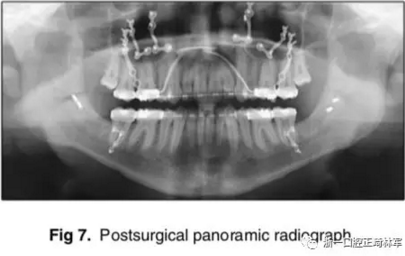

手術(shù)先采取下頜骨雙側(cè)矢狀劈開截骨術(shù),使用中間合板確定下頜位置。當下頜骨位置穩(wěn)定后,使用堅固內(nèi)固定固定下頜骨,移去中間合板。隨后,上頜行LeFort I型截骨術(shù),按照Dolphin軟件的計算前移7mm;通過終末合板確定上頜骨的位置,再使用鈦釘進行堅固內(nèi)固定。拔除第三磨牙;同時,在顴突處植入微鈦板,使用骨皮質(zhì)螺釘固定。

術(shù)后,患者即刻獲得了I類側(cè)貌,II類尖牙關(guān)系。